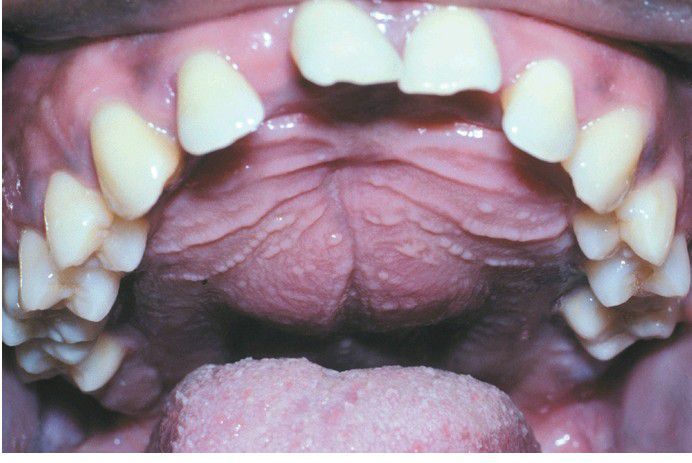

Palatal enlargement is characteristic of the renal osteodystrophy associated with secondary hyperparathyroidism.